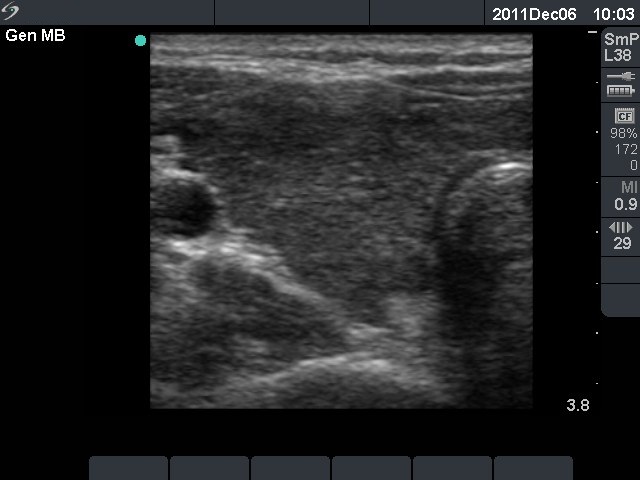

First investigation 6 months after delivery (first and second rows of images)

Clinical presentation: a 22-year-old woman was referred for an evaluation of a newly discovered hypothyroidism. She had fatigue and hair loss. She has been delivered 6 months before present investigation.

Palpation: the thyroids were enlarged and firm.

Functional state: hypothyroidism with TSH 47.7 mIU/L.

Ultrasonography: the thyroids were hypoechogenic without any nodule. The vascularization was increased.Cytology resulted in Hashimoto's thyroiditis.

Clinical diagnosis: hypothyroidism, post partum thyroiditis.